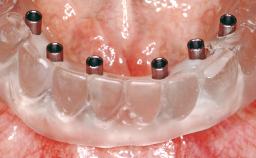

Immediate Loading of Six Implants in the Maxilla and Final Restoration with a Full-Arch CAD/CAM Zirconia FDP

# of Implants 6

Type of Implants One-Piece

Modality 6+ implants with immediate loading